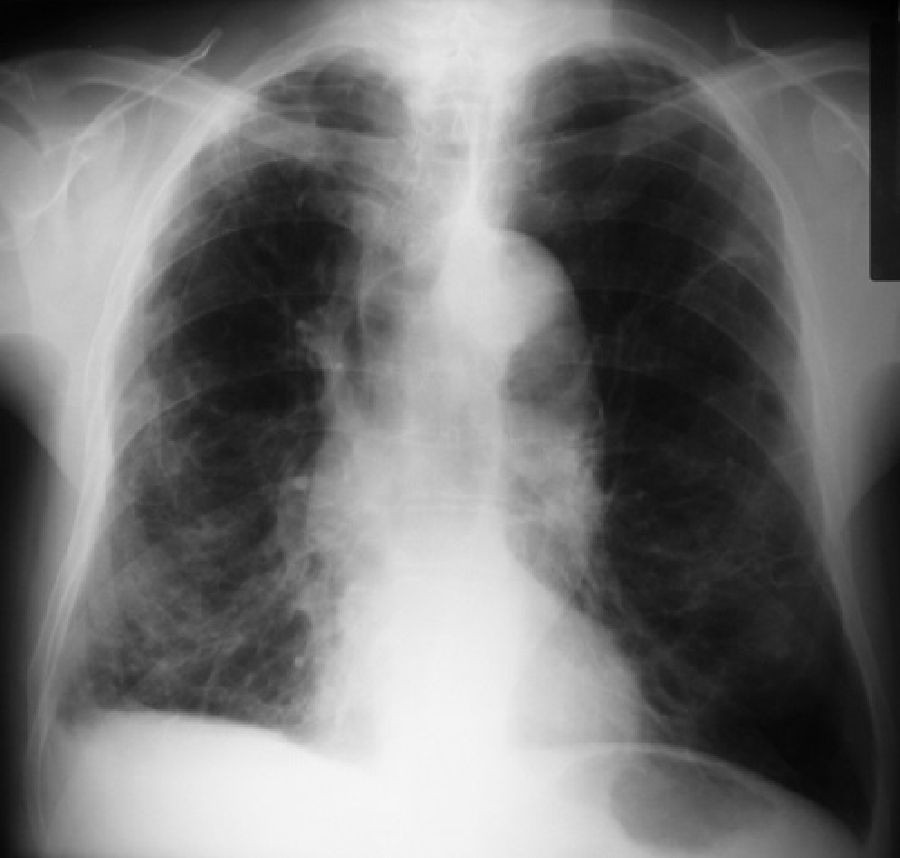

"Este trabajo, derivado del análisis cuidadoso de imágenes pulmonares de pacientes con EPOC, muestra que un desarrollo pulmonar anormal puede representar una gran proporción del riesgo de EPOC entre los adultos mayores --señala James Kiley, director de la División de NHLBI de Enfermedades pulmonares--. Se necesita más investigación para comprender qué impulsa este hecho y para idear posibles intervenciones".

Cada estudio, el Estudio Multiétnico de Aterosclerosis (MESA), el Estudio de los Pulmones, el Estudio de Subpoblaciones y Medidas de Resultados Intermedios en la EPOC (SPIROMICS) y el estudio de la Cohorte Canadiense de Enfermedad Pulmonar Obstructiva (CanCOLD), evaluaron la disanapsis usando tomografías computarizadas (CT) de los pulmones.